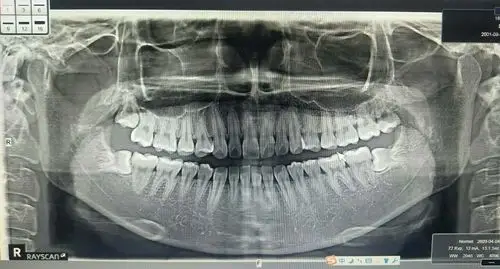

口腔全景片

2个版本的牙科全景x光片及前牙疼痛影像

牙科全景片

一张口腔全景片 求助